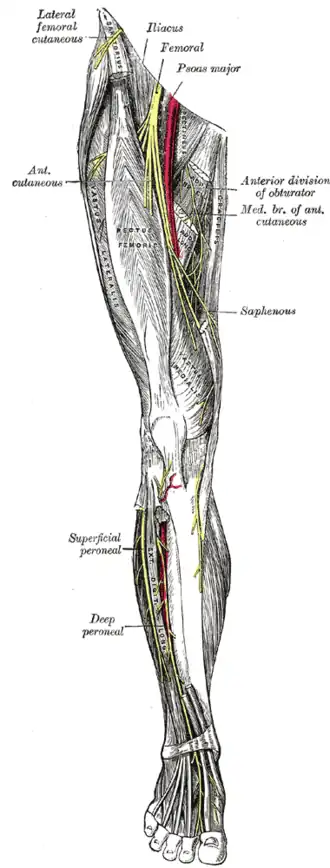

Le nerf saphène (ou nerf saphène interne dans l'ancienne nomenclature) est une branche terminale sensitive du nerf fémoral.

Le nerf saphène nait de la division terminale du nerf fémoral au niveau du ligament inguinal.

Le nerf saphène est satellite de l'artère fémorale au niveau du triangle fémoral. Il diverge de l'artère au niveau du canal des adducteurs en perforant septum intermusculaire vasto-adducteur. Il descend jusqu'à l'interligne articulaire du genou et perfore le fascia crural.

Il fournit des rameaux collatéraux : le rameau cutané fémoral, le rameau cutané tibial et le rameau articulaire pour le genou.

Il se termine en deux branches : le rameau infrapatellaire et le rameau crural.

Diagramme de la distribution segmentaire des nerfs cutanés de la plante du pied. Nerfs profonds à l'avant de la jambe.

Nerfs profonds à l'avant de la jambe. Nerfs du dos du pied.

Nerfs du dos du pied.